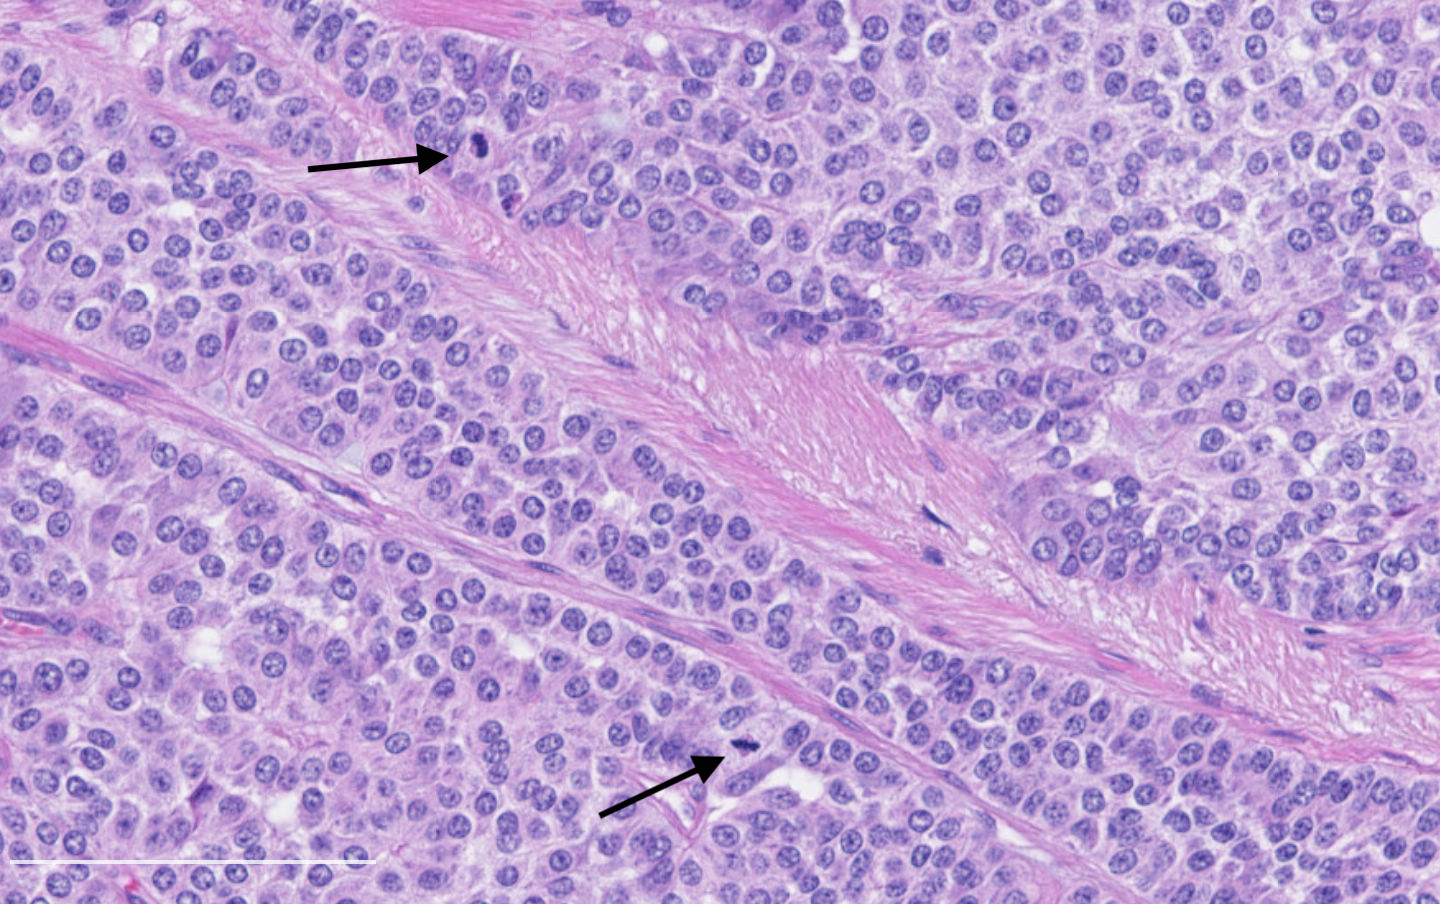

- Diagnostic criteria:

- Neuroendocrine morphology with 2 - 10 mitoses per 2 mm² or presence of necrosis

- Mitotic rate should be counted in the area with the highest proliferation rate (hot spot)

- Neuroendocrine histologic patterns similar to typical carcinoids: organoid, trabecular, rosette formation, papillary, pseudoglandular, follicular

- Tumor cells are as typical carcinoid: uniform with a polygonal shape, round to oval nuclei with salt and pepper chromatin and inconspicuous nucleoli, along with moderate to abundant eosinophilic cytoplasm

Contributed by Philippe Joubert, M.D., Ph.D.